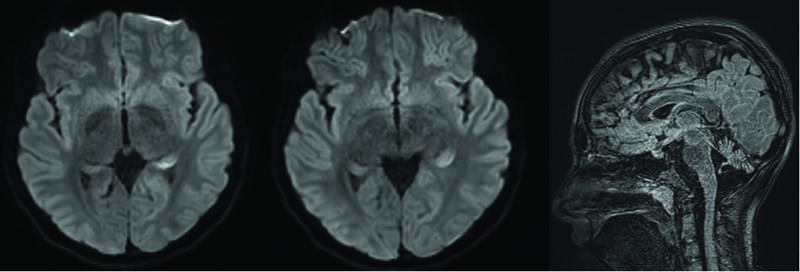

Owing to concerns for neurosarcoidosis, lymphoma, or vasculitis, a percutaneous stereotactic biopsy of a right occipital lesion was performed. Pathology revealed a demarcated CD68/163+ macrophage-rich lesion with myelin loss, relative axonal preservation, and a CD3+ predominant lymphocytic infiltrate with rare CD20+ B cells, consistent with active demyelination (Figure 2). She initiated a 5-day course of high-dose oral prednisone (1,250 mg daily) followed by a taper. Within 2 days of treatment, she experienced mild improvement in dysarthria and ataxia, although her EDSS score remained 6 on discharge.

Open in Viewer.